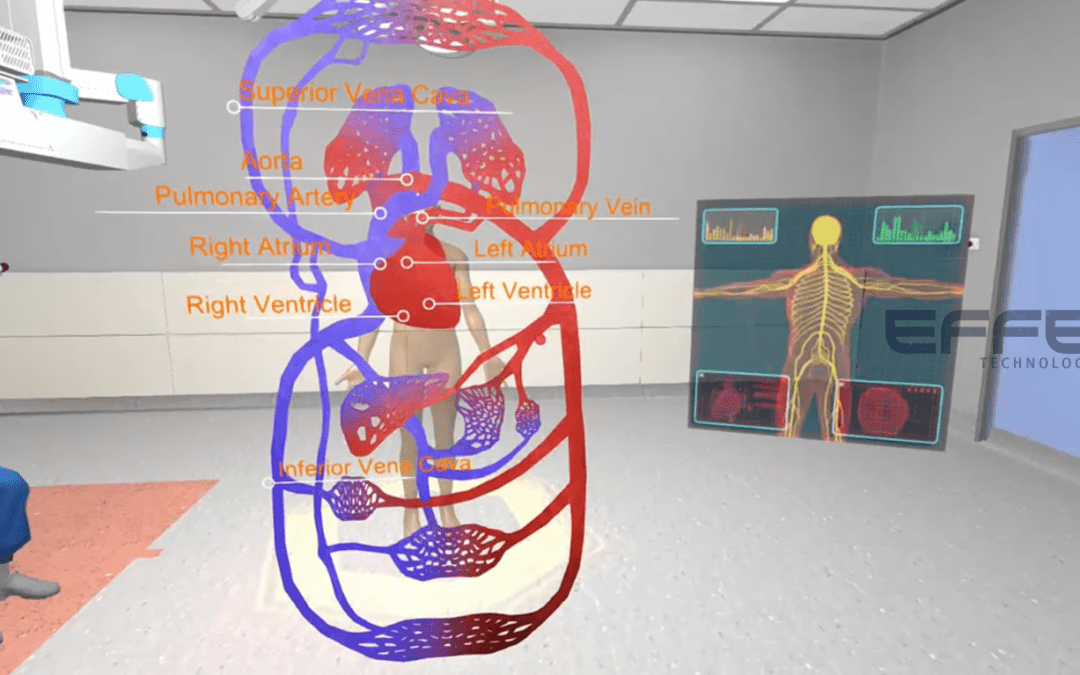

Overview Understanding pulmonary blood flow dynamics is critical for diagnosing and managing respiratory and critical...

Overview Understanding pulmonary blood flow dynamics is critical for diagnosing and managing respiratory and critical...